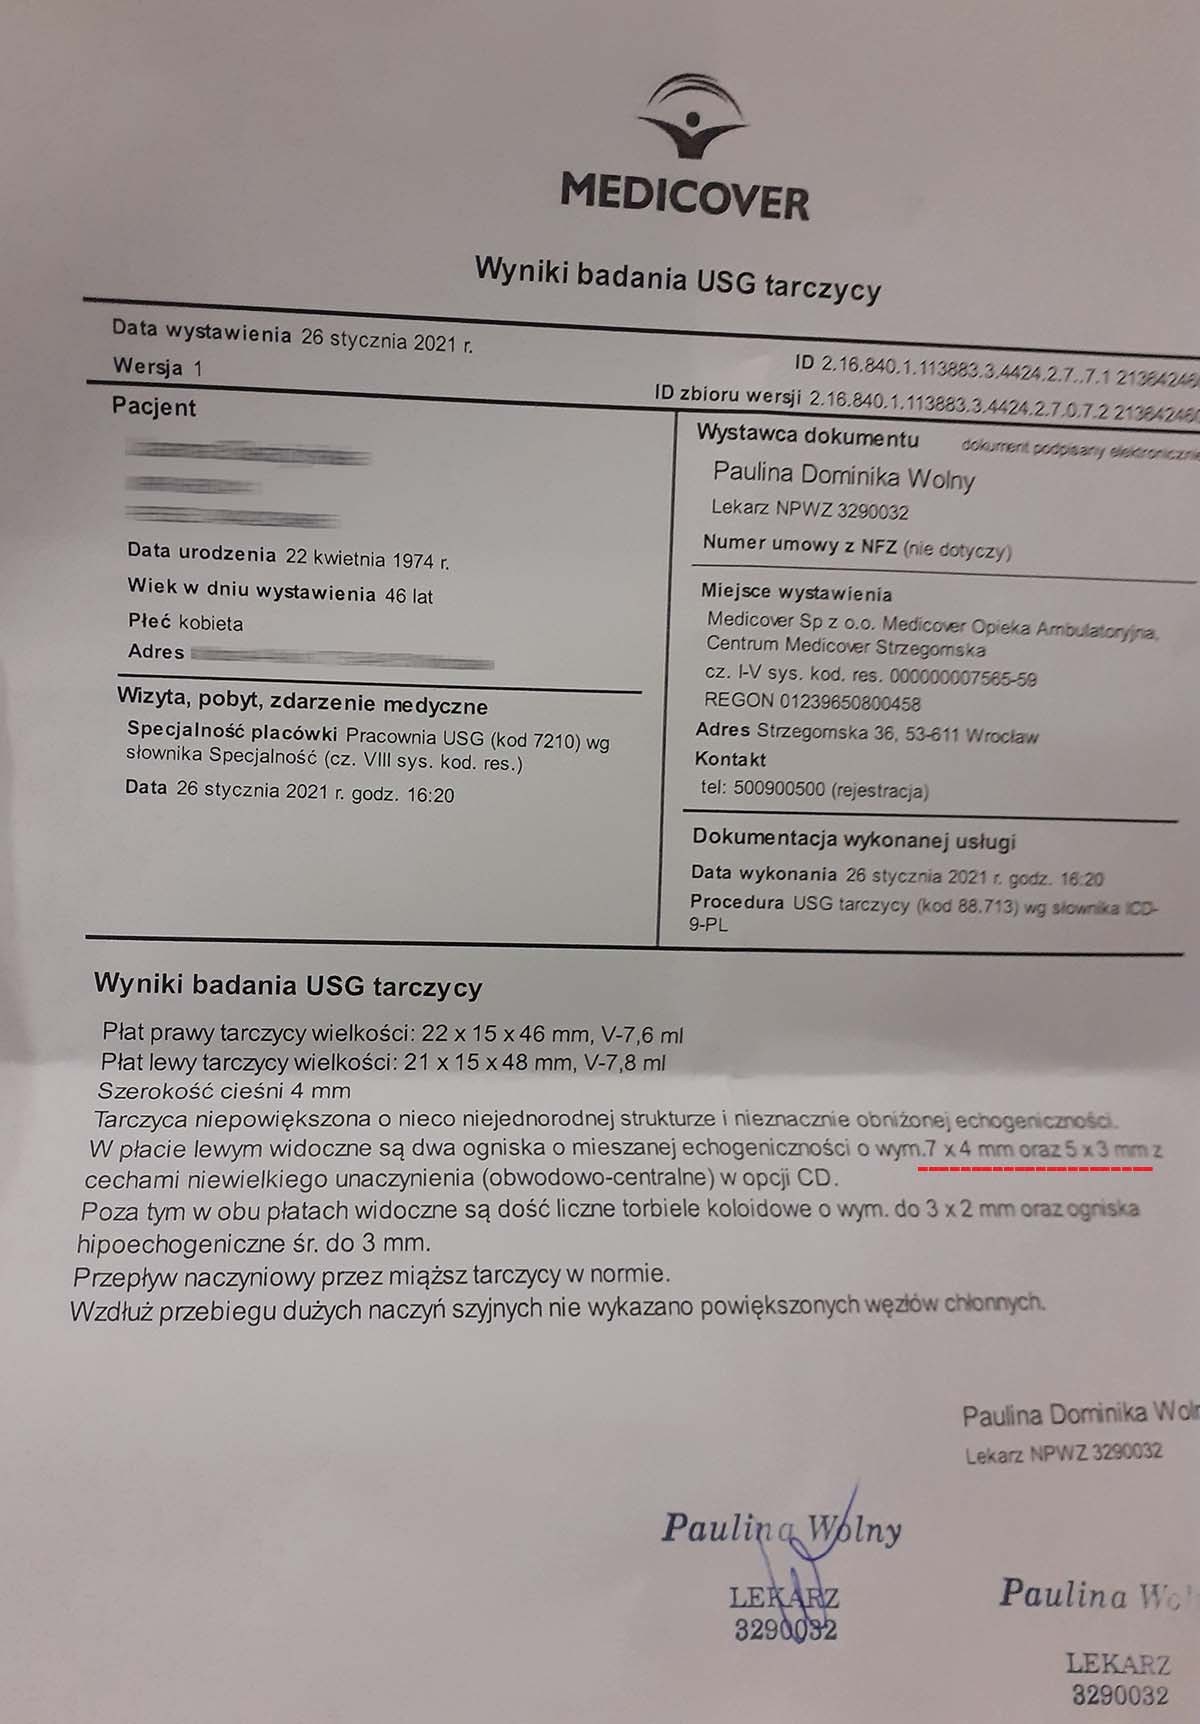

EFEKT PREPARATU PRZY GUZKACH NA TARCZYCY

Przypadek kobiety lat 46, przed podaniem preparatu wykryto guzki na tarczycy o wymiarach 9x4 mm i 5x8 mm, po zaledwie miesiącu stosowania bez dodatkowej farmakologii guzki zmniejszyły się do rozmiarów 7x4 mm i 5x3 mm. Szybka redukcja guzków (~20-65% ) bez ingerencji chirurgicznej i farmakologicznej wskazuje na naprawę komórkową na poziomie mitochondrialnym, co zapobiega nieprawidłowym podziałom komórkowym i rozwoju guzów. Preparat zwiększa wydajność mitochondriów do produkcji ATP, stymulując apoptozę uszkodzonych komórek, jednocześnie wpływając na regenerację i tworzenie poprawnych struktur. Jest to szczególnie wartościowe w przypadku guzów łagodnych, gdzie standardową procedurą jest jedynie obserwacja zmian, co najczęściej prowadzi do rozwoju znacznie trudniejszych do opanowania nieprawidłowości.